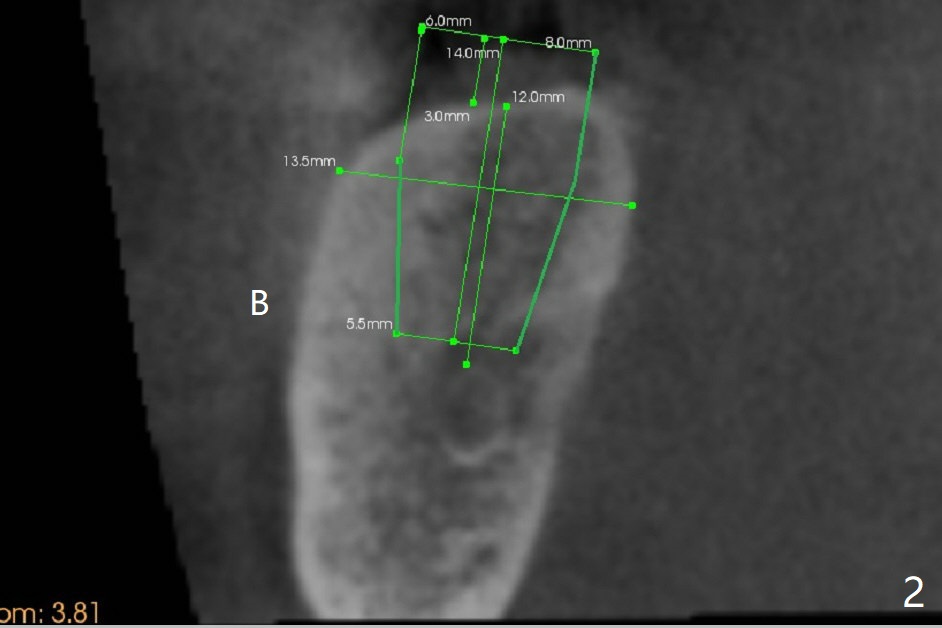

A 69-year-old man needs an implant at #18 (Fig.1,2 CT (sagittal and coronal sections)). In spite of use of surgical stent, the trajectory is not ideal (Fig.3-5). The following day the implant is removed with bone graft (Fig.6). In the 2nd placement, the trajectory is adjusted in each step (Fig.7-9 arrows) with long term stability (Fig.10,11).